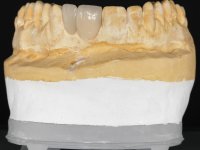

A two element bridge was suggested, using tooth 2.1 as abutment and tooth 2.2 as cantilever pontic. Cantilever bridge with ceramic-coated Zr infrastructure.

Arcade prints were made with irreversible hydrocolloid, for the lab to prepare an acrylic provisional bridge, with tooth 2.1 as abutment and tooth 2.2 as cantilever pontic. A palatal support was made to be bonded with the palatal surface of tooth 2.3. After removal of the Maryland bridge and the vestibular veneer from tooth 2.1, the dental abutment was re-prepared by making the cervical finish line intrasulcular. The provisional bridge made in the lab was relined on the mouth with self-curing acrylic and composite resin. During 6 weeks the soft tissues were worked and stabilized, preparing the consultation for impression. In this session, gingival separation was performed with kaolin paste, using the provisional bridge to compress the material into the gingival sulcus. Impression was performed using wash technique, and the provisional bridge was placed. At the end of the consultation, an impression was made from the provisional bridge placed in the mouth, using irreversible hydrocolloid. The patient had approved the aesthetics of the provisional. This information was passed on to the lab, where the work followed a silicone index, based on the shape and arrangement of the provisional bridge, approved by the patient. The cantilever bridge was built with a Zr infrastructure, with particular care in designing the connector. After being tried and approved by the patient, the prosthetic was cemented in the mouth with resin modified glass ionomer.